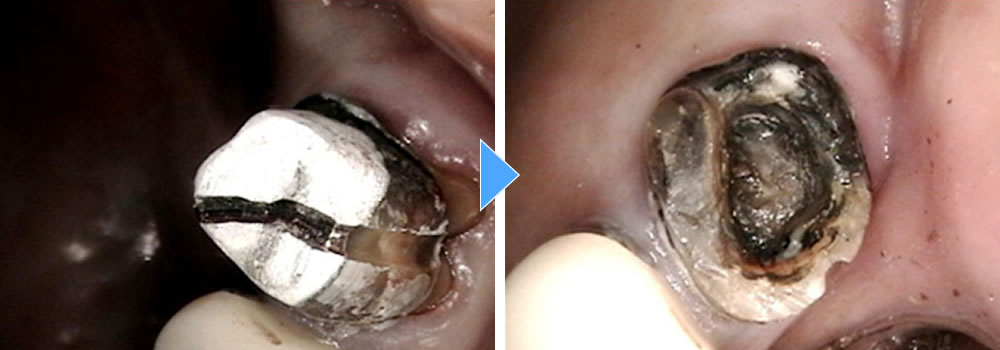

再発虫歯の治療後にセラミックアンレーで修復した症例

むし歯が再発した銀歯をセラミックインレーで治療した症例 こちらの患者さまは、初診の際にレントゲンをお撮りしたところ、保険のインレーの下にむし歯が認められたため、治療することとなりました。 むし歯の除去 1回目の治療にて保 […]